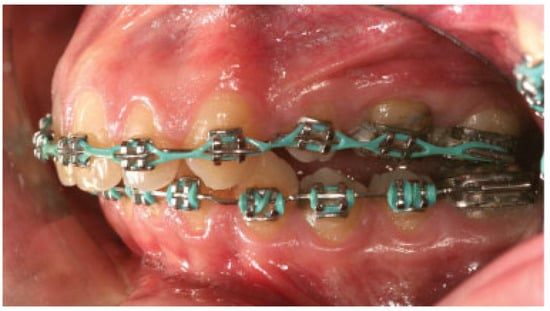

:Case Report